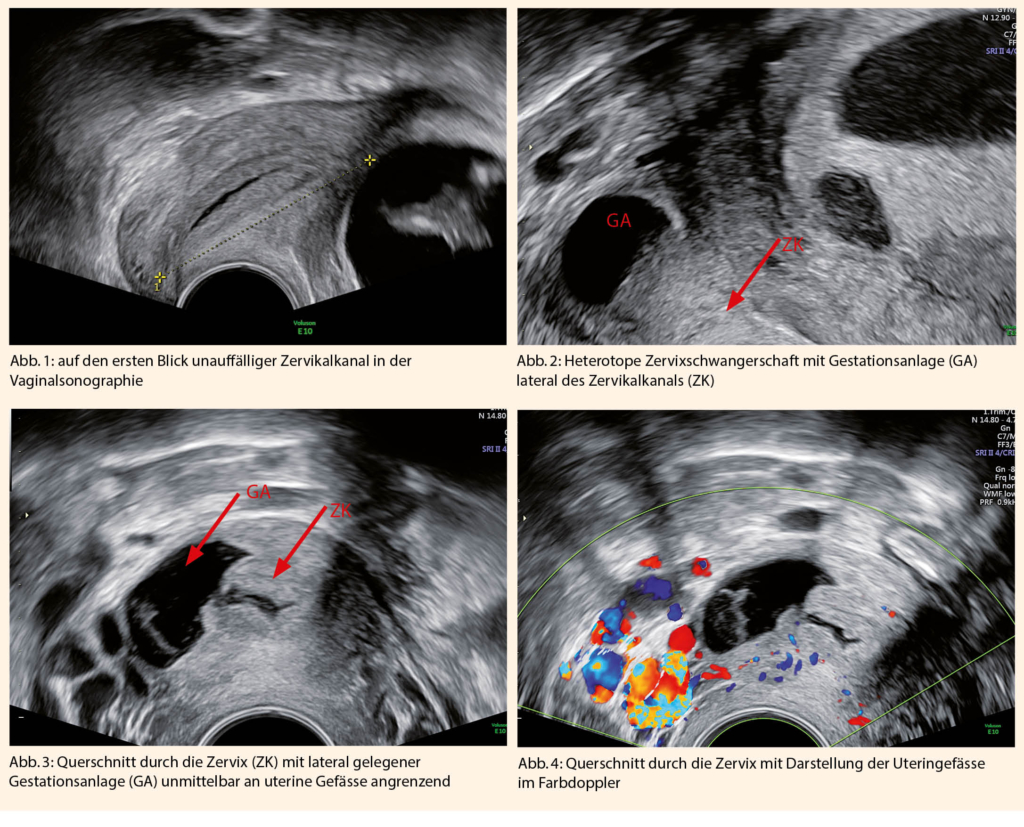

Auch hier bestand die Situation, dass die zervikale Anlage nicht auf einen ersten Blick zu erkennen war (Abb.1). Es präsentierte sich ein vitaler, sonomorphologisch unauffälliger und zeitgerechter Fetus mit regelrechter intrauteriner Implantation mit einer Scheitel-Steiss-Länge von 46 mm und einer unauffälligen Morphologie. Gleichzeitig stellte sich eine missed Abortion im caudalen Drittel der Zervix rechts lateral mit einer avitalen Embryonalanlage und einer Scheitel-Steiss-Länge von 10 mm dar. (Abb. 2)

Besonders war die Lokalisation der Zervixschwangerschaft. In den bisher publizierten Fällen war sie zentral in der Zervix gelegen. In diesem Fall lag sie im caudalen Drittel der Zervix mit einer lateralen Unterbrechung der Kontinuität der Zervixwand wodurch die Trophoblastgrenze unmittelbar an die aufsteigenden rechten Uteringefässe (Abb. 3 und 4) angrenzte. Gleichzeitig war sie von Abdominalsonographisch sowie in der Standardeinstellung des Zervikalkanals nicht ohne weiteres zu erfassen.